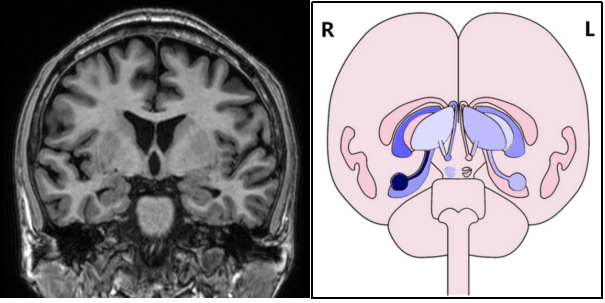

图3:65岁患者,因认知功能降低,常规头颅MRI图像(左图)MTA评分0分,精神影像(右图)后处理显示其右侧海马萎缩超过10%,后证实为MCI(轻度认知损害)